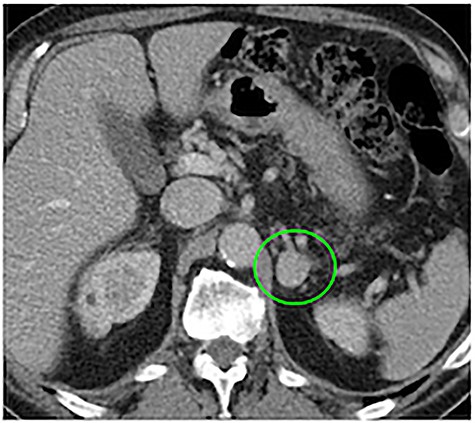

The patient reported a previous history of left non-secreting adrenal incidentaloma, diagnosed 10 years before. At the time of diagnosis, the tumor diameter was 2.3 cm, with CT densitometry suggestive for benign adenoma (Fig. 2); the patient had been invited to regular follow-up visits, which he never attended. After 6 years, a new contrast CT demonstrated a growth of the tumor up to 7 cm. The clinical examination had excluded symptoms and signs of adrenal hormonal excess. A new complete evaluation of the endocrine situation was repeated: 1 mg overnight dexamethasone suppression test excluded cortisol excess; pheochromocytoma was excluded by the measurement of urinary fractionated metanephrines; because the patient was hypertensive, aldosterone/renin ratio was performed after 2-month washout from interferent antihypertensive drugs and a primary aldosteronism was excluded; all other laboratory tests were regular. The patient was asymptomatic and decided to discontinue his follow-up, coming back to medical attention the day of the trauma. After treatment of the hemothorax, the patient recovered completely and was discharged. Subsequently, he was submitted to abdominal open surgery through an anterior approach. A Chevron bilateral subcostal incision was made; the left colon mobilized, with careful dissection of the mesocolon from the mass. The left retroperitoneal space was accessed, displaying an imposing vascularized mass occupying the upper left abdomen (Fig. 3a–d). The mass displaced the left kidney, determining a verticalization downward of the left renal artery and vein and was in close contact with the upper pole of the kidney without having clear cleavage plans (Fig. 1b). On the other hand, the splenic artery and vein were displaced vertically upward. Careful dissection of the mass allowed its complete removal without damaging the surrounding organs and vessels, with ligation of the adrenal vein (Fig. 3d), as well as large lumbar vessels vascularizing the mass. Blood loss was 2500 cc, and the patient was transfused with 5 units of concentrated red blood cells. Final dimensions of the mass on the operating table were 26 × 21 × 12 cm, weight = 4.5 kg (Fig. 4). Two abdominal drains were left in place and removed on the fourth and fifth postoperative day. The postoperative clinical course was uneventful, and the patient was discharged on the seventh postoperative day without complications. At 6-month follow-up visit, the patient presented no symptoms and no signs of recurrence.

Ten years before abdominal CT scan, provided by the patient, at the time of first diagnosis, showing a 2.3-cm mass at the level of the left adrenal gland (green circle).